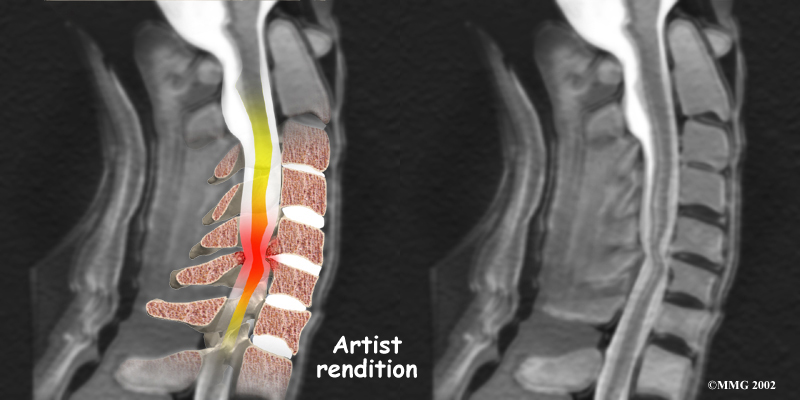

The nucleus may push through the weakened and torn annulus and into the spinal canal. This is called a herniated or ruptured disc. The disc material that squeezes out can press against the spinal nerves. The disc also emits enzymes and chemicals that produce inflammation. The combination of pressure on the nerves and inflammation caused by the chemicals released from the disc cause pain.

If the herniated disc material presses against a nerve root it can cause pain, numbness, and weakness in the area the nerve supplies. This condition is called cervical radiculopathy (mentioned earlier). And any time the herniated nucleus contacts tissues outside the damaged annulus, it releases chemicals that cause inflammation and pain. If the nucleus herniates completely through the annulus, it may squeeze against the spinal cord. This causes a condition that is even more serious because it affects all the nerves of the spinal cord. This condition is called cervical myelopathy.

Stenosis means closed in. Spinal stenosis refers to a condition in which the spinal cord is closed in, or compressed, inside the tube of the spinal canal. Spinal stenosis may be caused by degenerative changes, such as bone spurs pushing against the spinal cord within the spinal canal.

Spinal Stenosis

However, stenosis can also develop when a person of any age has a disc herniation that pushes against the spinal canal. When the spinal cord is squeezed in the neck, doctors call the condition cervical myelopathy. This is an alarming condition that demands medical attention. Cervical myelopathy can cause problems with the bowels and bladder, change the way you walk, and affect your ability to use your fingers and hand.

Cervical Myelopathy